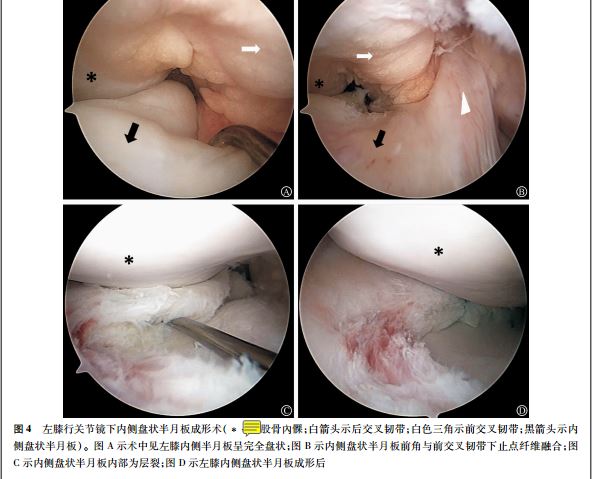

病例三 双膝内侧盘状半月板,仅一侧有症状。

患者男 性, 17 岁, 学生, 无特殊运动爱好史, 因“双膝不适感 10 余年, 左膝疼痛、 伸直受限 1 个月余”入院。 。 双膝 MRI 提示: 左膝内侧盘状半月 板撕裂伴前角 囊肿, 右膝内侧盘状半

月 板伴变性 。 因患者左膝疼痛及伸直受限,而右膝关节无明显症状, 不影响日 常生活及活动, 故

行左膝关节镜下内侧盘状半月 板成形术。